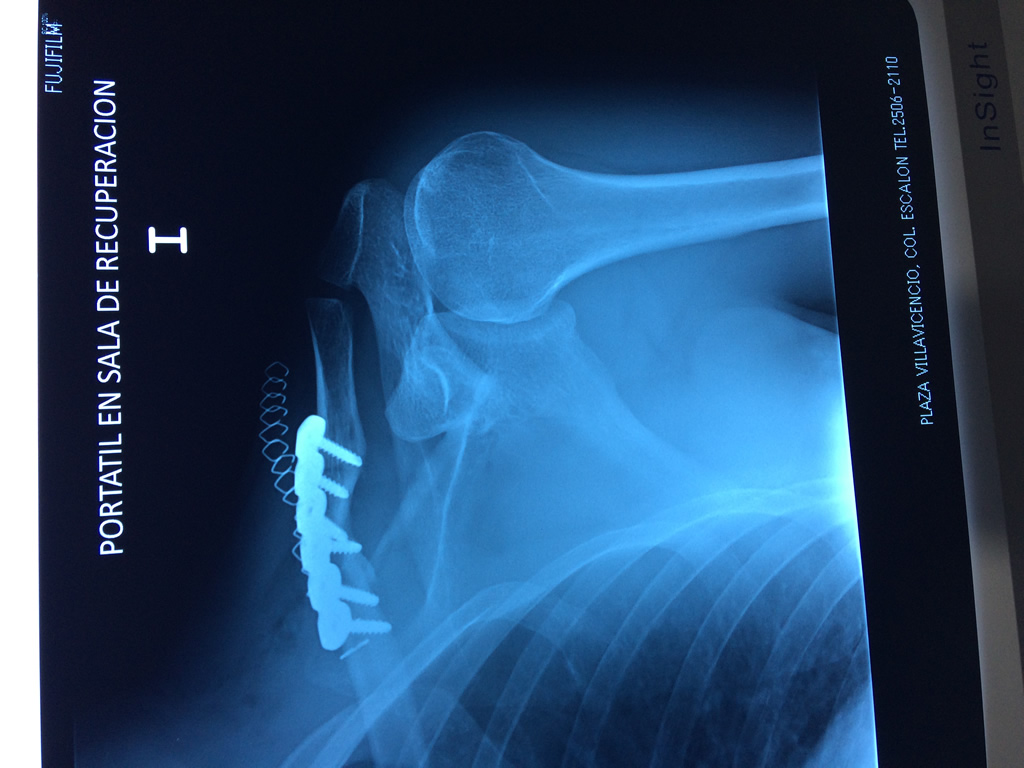

Cirugías de Húmero - Clavícula